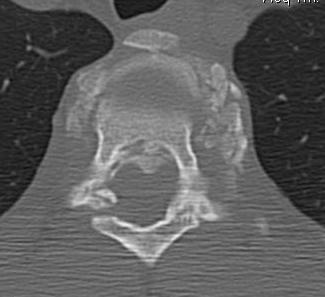

CT

Look for canal compromise

- cord signal change

- kyphotic deformity

Retropulsed fragments

- always between pedicles

- typically one or two main fragments (saloon door)

- assess canal compromise